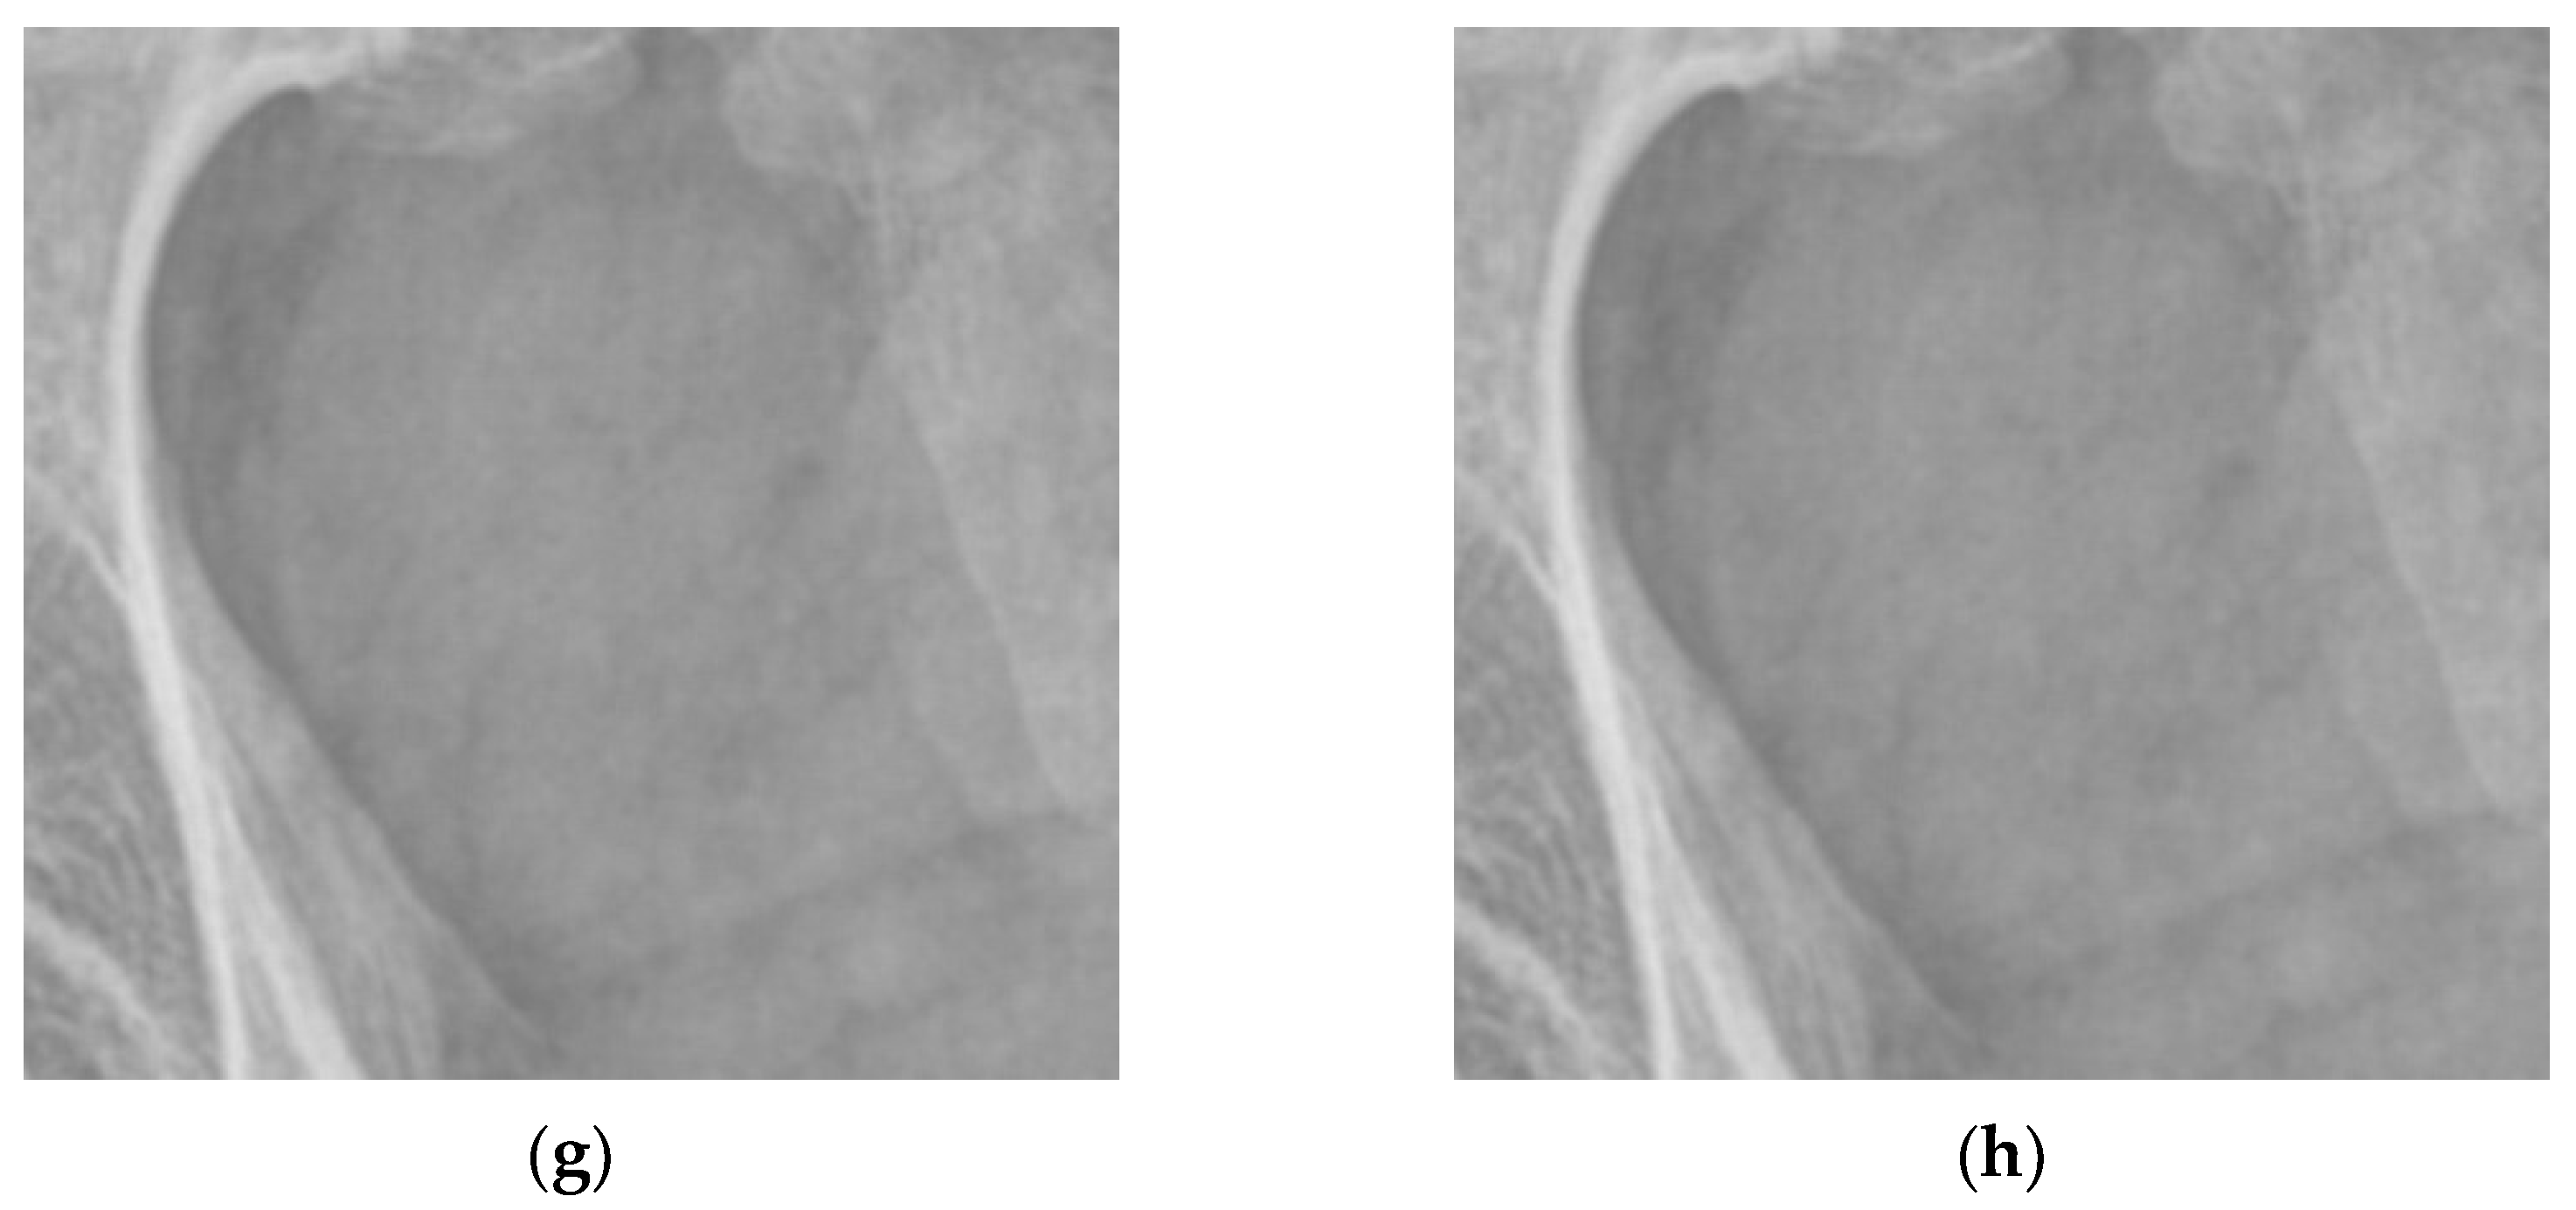

4.1. Simulations for Multicale Diagnostic Detail Enhancement on DR Images